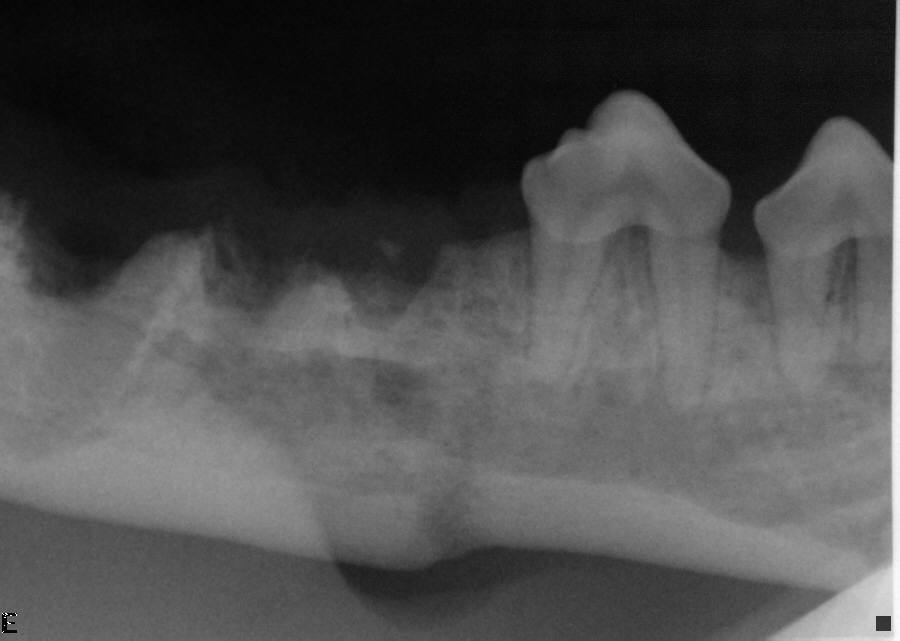

After fracture healing, periodontally and endodontically compromised teeth were removed.

Intraoral radiograph after extractions of endodontically compromised first molar and periodontally compromised fourth premolar teeth. Notice the healed fracture line despite the initial fracture gap.